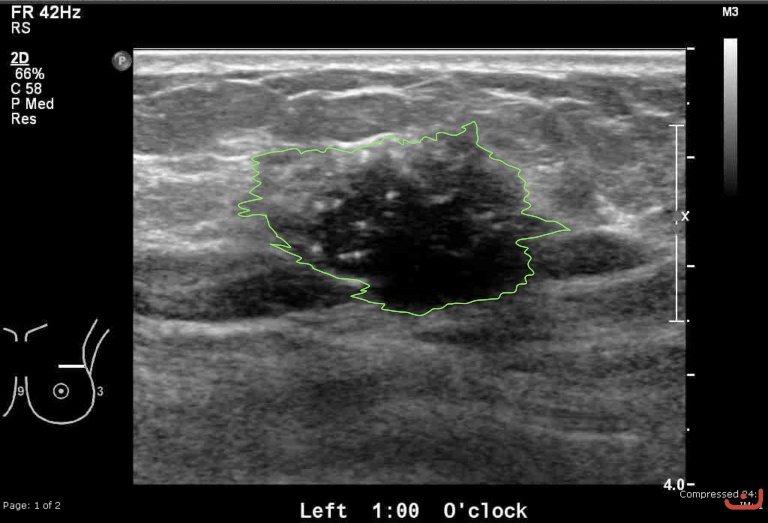

Case 45-G1

Malignant solid mass

Friday, 22 May 2015

191.47 KB (768 x 523 px)